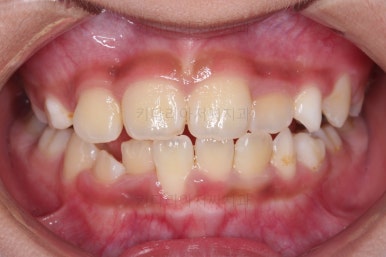

1. 초진

초진 시 입안의 모습입니다.

가장 눈에 띄는 건, 아랫니가 윗니보다 앞에 나와있는 부정교합인데요.

반대교합이 주로 좌측 앞니쪽에서 있다보니 해당 부위로 아래턱이 밀리면서 앞모습에서 비대칭도 보입니다.